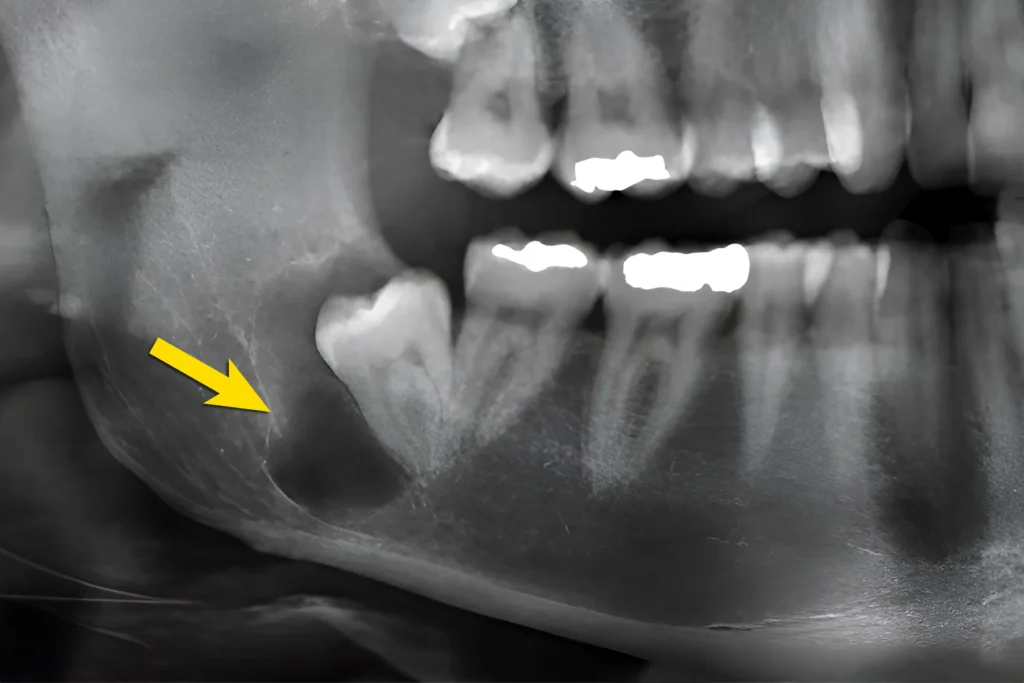

Rozpoznanie torbieli opiera się na badaniu klinicznym oraz diagnostyce obrazowej. Stomatolog wykonuje zdjęcie pantomograficzne lub kieruje pacjenta na diagnostykę CBCT. Badanie trójwymiarowe pozwala dokładnie określić wielkość zmiany oraz jej relację do struktur anatomicznych.

Stomatolog może również rozpoznać torbiel związaną z zatrzymanym zębem, na przykład ósemką. W takich przypadkach zmiana rozwija się wokół korony niewyrzniętego zęba i może stopniowo powiększać się w obrębie kości.